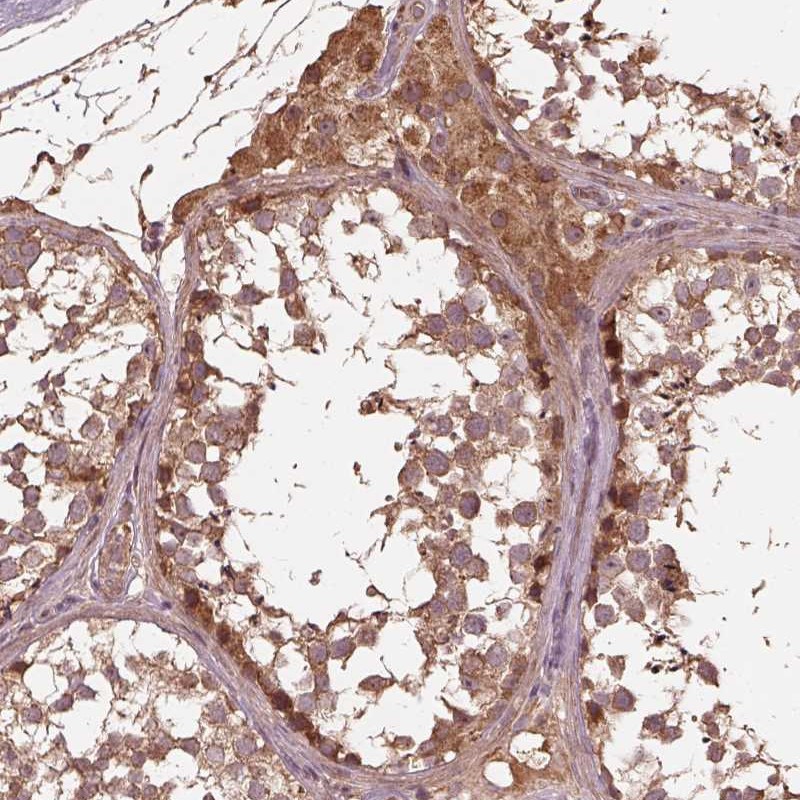

Immunohistochemical staining of human testis shows strong cytoplasmic positivity in cells in seminiferous ducts and Leydig cells.